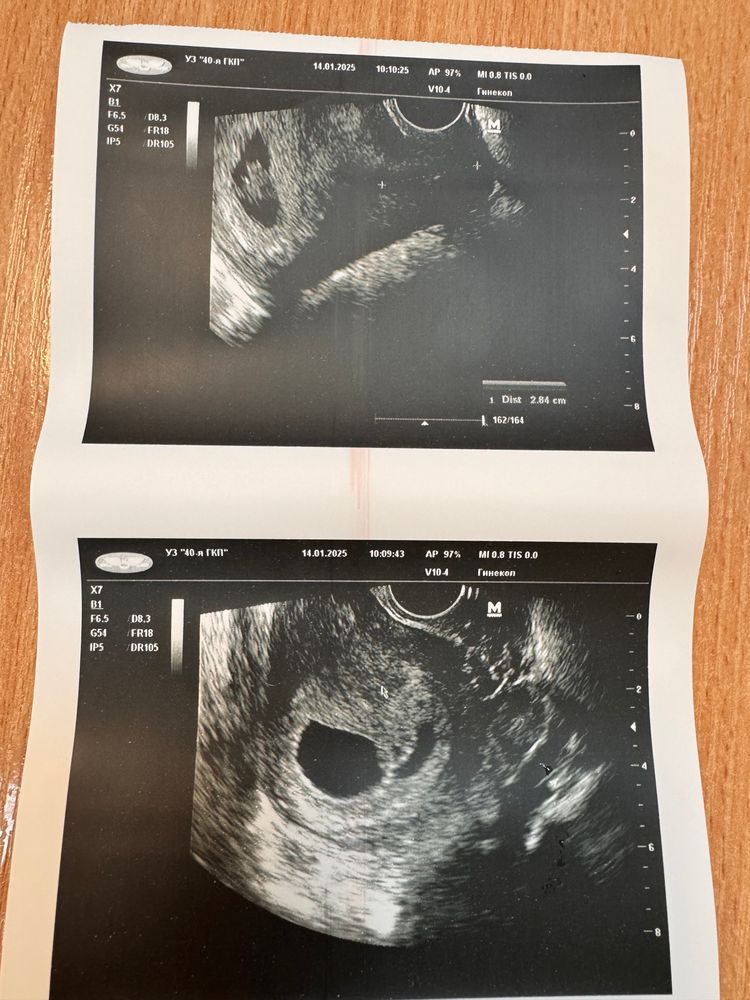

14.01 у меня была явка в Жк, болезнь вроде как начала отступать, герпес прошел, глаза практически тоже, а кашель, ну он остался, но хоть нет зеленой мокроты, взяли мне мазки, выдали кучу анализов и пошли на узи, чтобы впервые послушать сердечко малыша.

Я была спокойна,но при проведении узи меня удручала тишина врача и что я не слышу никаких звуков вообще, сразу мысли в голове.. нет сердцебиения?? Потом озвучиваю вслух, вы не можете найти сердечко? А она : не переживайте, наверное ночной режим, сейчас еще позову врача, в общем пришла еще одна девушка и меньше чем за минуту тыкает в экран и показывает, вот, есть пульсация, я выдохнула, но меня знатно перетрясло, но они начали обсуждать, что по узи им не нравится участок, похожий на отслойку, нужно госпитализироваться, тут снова я начала паниковать, как так, что за отслойка, меня же ничего не беспокоит и выделений никаких нет, фото узи вставлю ниже :

Вот то самое узи от 20.01, которое убило меня ..